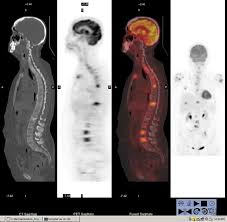

Fdg Pet Pet Ct And Breast Cancer Imaging Radiographics from pubs.rsna.org A breast pet scan is often very specific and sensitive and is approved for patients. It's an effective imaging test for finding cancer and learning its stage. Bone scans, positron emission tomography (pet), and computed tomography (ct) all continue to be employed alone or in combination for the detection of breast cancers suspected to have spread. Breast positron emission tomography (pet) scan is an imaging test that uses a tracer (radioactive substance) to look for symptoms of breast cancer. Pet scan is a type of test that may be used in cancer treatment. Pet scans can be used to determine how much cancer is in a person's body and how far the cancer has spread, which is called staging. It can be done along with a ct scan. Pet scans can be useful for evaluating people after breast cancer has already been diagnosed, in a number of different ways:

For cancer, pet is especially useful as it can scan the entire body and pinpoint both a primary tumor and areas of metastasis (where the cancer has spread).

The test has only a limited ability to detect small tumors. Pet scan for breast cancer a positron emission tomography (pet) scan is an imaging test that uses a radioactive substance (called a tracer) to look for potential spread of breast cancer. In some instances, cancers may not show on the scan. Combining a pet scan with an mri or ct scan can help make the images easier to interpret. Pet scans can be used to determine how much cancer is in a person's body and how far the cancer has spread, which is called staging. This tracer can help identify areas of cancer that an mri or ct scan may miss. With cancer cells, they appear as bright spots due to its higher metabolic rate compared to normal cells. However, the pet scan uncovers every unusual activity in the body and is more sensitive than any other existing imaging test. Pet/ct scan can accurately localize lymph node metastasis and help to monitor the response to chemotherapy. Breast positron emission tomography (pet) scan is an imaging test that uses a tracer (radioactive substance) to look for symptoms of breast cancer. Pet scans can also help to assess whether metastatic breast cancer is responding to the treatment. Pet scans are not used to screen women for breast cancer. Pet/ct scans using axumin tracer, approved by fda last year and newly approved by medicare in some areas, are starting to be done at different locations.

The Clinical Utility Of Fdg Pet Ct In Follow Up And Restaging Of Breast Cancer Patients Sciencedirect from ars.els-cdn.com Pet scan is a type of test that may be used in cancer treatment. A ct scan produces multiple images, providing a detailed picture of the internal anatomy, including the location of cancerous growths. If you have a large breast cancer, your doctor may order a ct scan to assess whether or not the cancer has moved into the chest wall. This substance is often called a tracer, because it helps reveal cancer in the body. It is similar to a pet scan, but it uses a different radioactive substance that settles in areas of change in the bones. For cancer, pet is especially useful as it can scan the entire body and pinpoint both a primary tumor and areas of metastasis (where the cancer has spread). In some instances, cancers may not show on the scan. When breast cancer cancer spreads.

Is Radiation From A Ct Or Pet Scan Dangerous Cancer Ut Southwestern Medical Center from s3-us-west-2.amazonaws.com It is common for patients to receive a diagnosis for cancer of unknown primary. Pet scans can be useful for evaluating people after breast cancer has already been diagnosed, in a number of different ways: Types of cancer detected and treated. I am wondering, and never asked the oncologist about this. Bone scans, positron emission tomography (pet), and computed tomography (ct) all continue to be employed alone or in combination for the detection of breast cancers suspected to have spread. At left is a ct scan, while the center image is from a pet scanner. However, you may hear your doctor refer to this procedure just as a pet scan. Its supposed to be more sensitive/specific than naf and other older scans, and comparable i think to choline or acetate (lots of studies and info on the web) and.